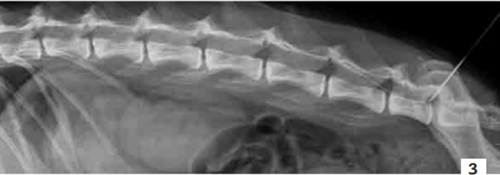

Il est possible d’administrer ce mélange de manière prolongée, aussi longtemps qu’il est jugé nécessaire, en posant un cathéter péridural (photo 3) [21]. La quantité de principe actif à injecter est alors calculée en se fondant sur celle de morphine à administrer. La concentration de la solution de morphine est de 2 mg/ml. La dose nécessaire est de 0,3 mg/kg/24 h. Une fois le volume de morphine calculé, la même quantité de bupivacaïne 0,5 % est ajoutée. Le mélange est alors administré sur 24 heures à l’aide d’un pousse-seringue [9].

Photo 3 - Cliché radiographique de profil de la colonne lombaire d’un chien.

Noter le cathéter péridural qui permet de compléter le protocole analgésique avec un anesthésique local associé à un morphinique par voie péridurale.

Photo : C. Bille